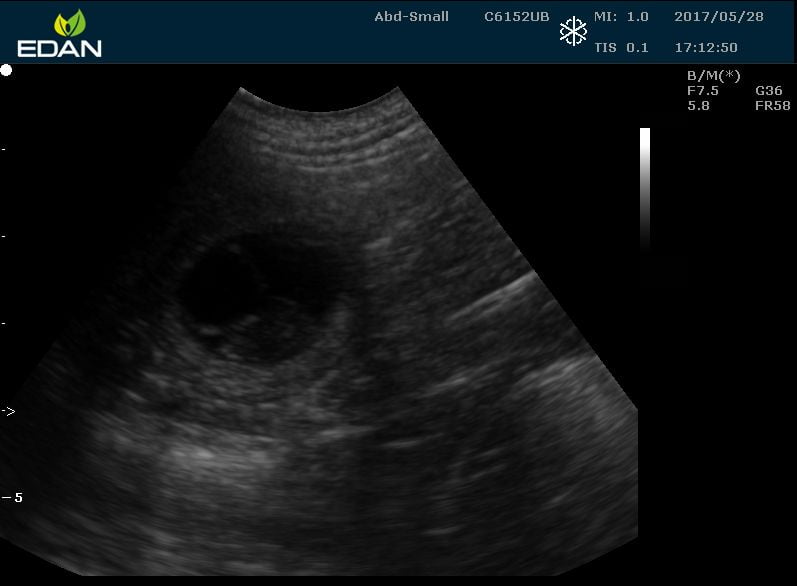

An early pregnancy in a bulldog, around 30 days. The measurement markers at the side show that the gestation sacs are only 2-3cm long. Bone ossification has not yet begun.